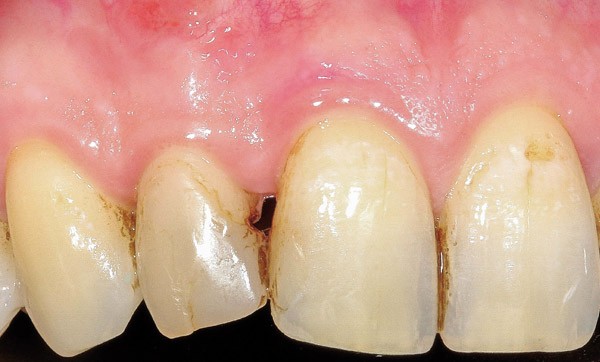

Il est fréquent de recevoir des patients pour des problèmes d’édentements antérieurs unitaires. L’étiologie de cet édentement peut avoir différentes origines ; de façon non exhaustive, on peut citer des causes endodontiques, parodontales ou des fractures radiculaires. Les solutions proposées de nos jours sont nombreuses, de la prothèse amovible à la thérapeutique implantaire en passant par les bridges conventionnels ou collés. La solution implantaire reste souvent la solution de choix car non mutilante pour les dents adjacentes.

Examen clinique

Il convient d’observer particulièrement :

– au niveau occlusal, la présence de zones d’usure pouvant indiquer la présence d’un bruxisme ou de parafonctions ;

– au niveau esthétique : la situation de la ligne du sourire, haute, moyenne ou basse ;

– au niveau prothétique : l’espace inter-arcades afin de déterminer la hauteur occlusale prothétique utilisable (HOPU) ;

– au niveau parodontal : le type de parodonte, fin ou épais, la quantité de gencive attachée.

En fonction de ces évaluations, des traitements pré- implantaires permettant une mise en place dans un couloir prothétique fonctionnel et la gestion de l’esthétique peuvent se révéler nécessaires.